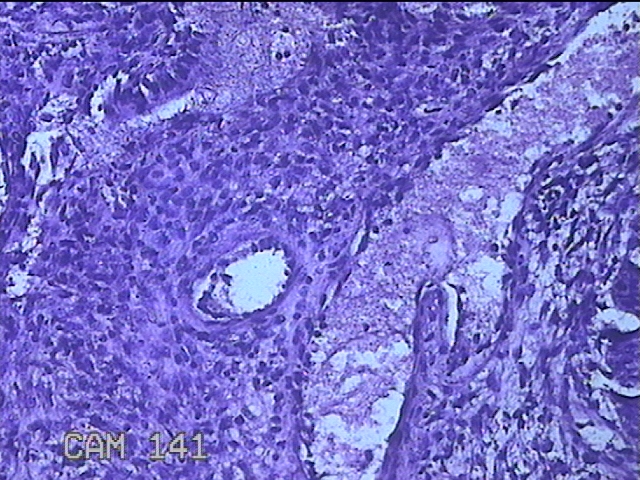

宫颈赘生物

性别

女

年龄

36岁

临床诊断

一般病史

发现宫颈赘生物1个月。

标本名称

大体所见

灰白暗红色肿物1x0.7x0.2cm一个,表面糜烂。

图1